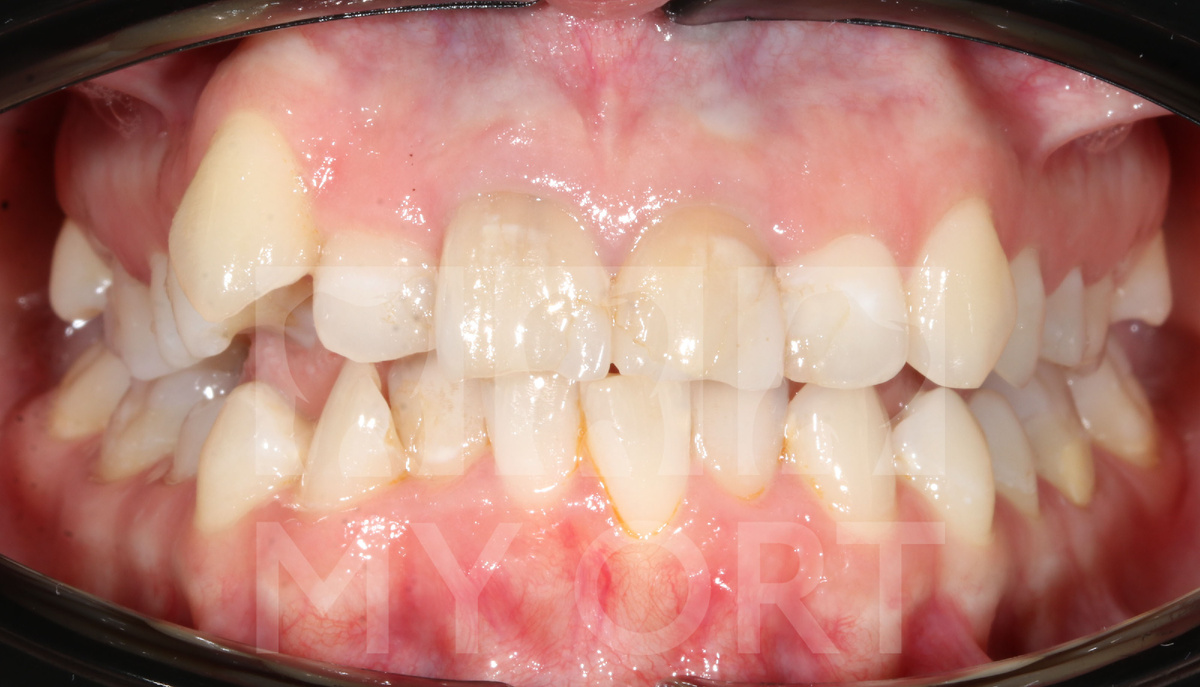

Чего мы смогли добиться после трёх с половиной лет лечения:

1. Болевой синдром в суставе был полностью устранен.

2. Функция височно-нижнечелюстного сустава стабилизировалась.

3. Устранена скученность зубов.

4. Была достигнута эстетика зубов и улыбки.

До и ПОСЛЕ лечения. Результат после 3.5 лет

Пациентка осталась счастлива. Самое главное, что боли ее больше не беспокоят. У нее был период небольшого обострения, я ей подсказала и объяснила, что необходимо делать, для поддержания мышечного баланса и стабильности сустава. Сейчас у нее все прекрасно и абсолютно все стабильно.